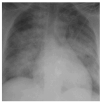

Fig. 1. Radiografía de tórax que muestra signos de edema pulmonar bilateral sin cardiomegalia.